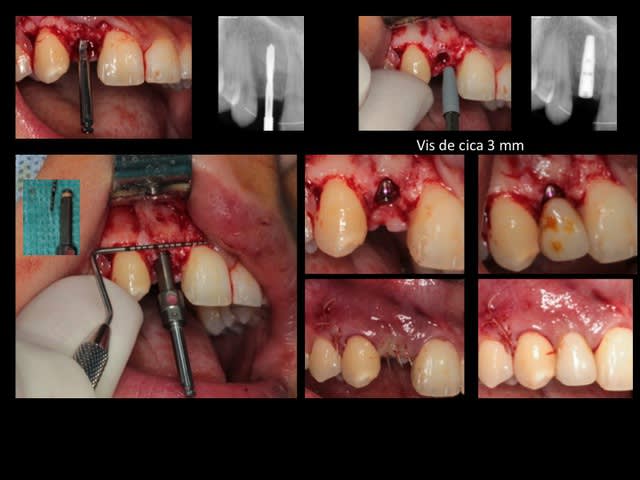

la suite et le début:

scan pré op: pas bcp d'os dispo au niveau de 46 47, y'a fallu aller plus loin derrière

la 11: voir son axe et le peu d'os autour en vestibulaire

photo de la cica à quelque mois

bientôt scan et pose de l'implant